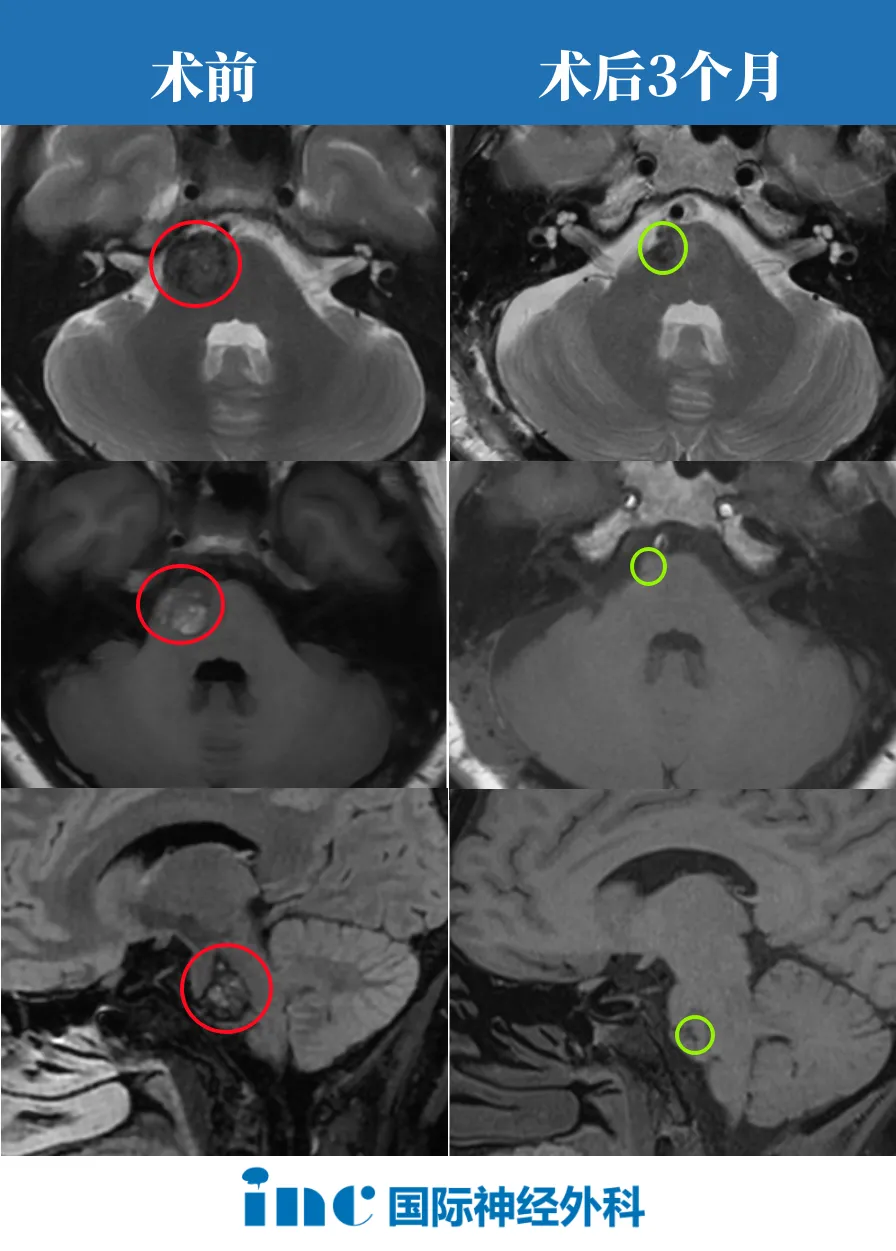

先來看看這個(gè)案例,29×39×38 mm,一個(gè)大型巖斜區(qū)腦膜瘤像一個(gè)小山丘一樣,山頂直接擠壓“生命禁區(qū)”腦干,還與神經(jīng)血管結(jié)構(gòu)緊密粘連。此時(shí)的他僅有頭痛癥狀。

其實(shí)不然,在INC福教授的定制化手術(shù)策略之下,無需開顱,僅右側(cè)單鼻孔入路便全切腫瘤。腦干復(fù)位良好,未見腦脊液漏及新發(fā)神經(jīng)功能障礙。

腦膜瘤影像

福教授采用開顱手術(shù),術(shù)前通過線圈在咽升動(dòng)脈處進(jìn)行栓塞,可以顯著減少術(shù)中出血。在切除腫瘤過程中,使用CUSA刀對(duì)腫瘤逐漸減瘤。術(shù)后MRI顯示腫瘤幾乎完全切除,腦干受壓解除。